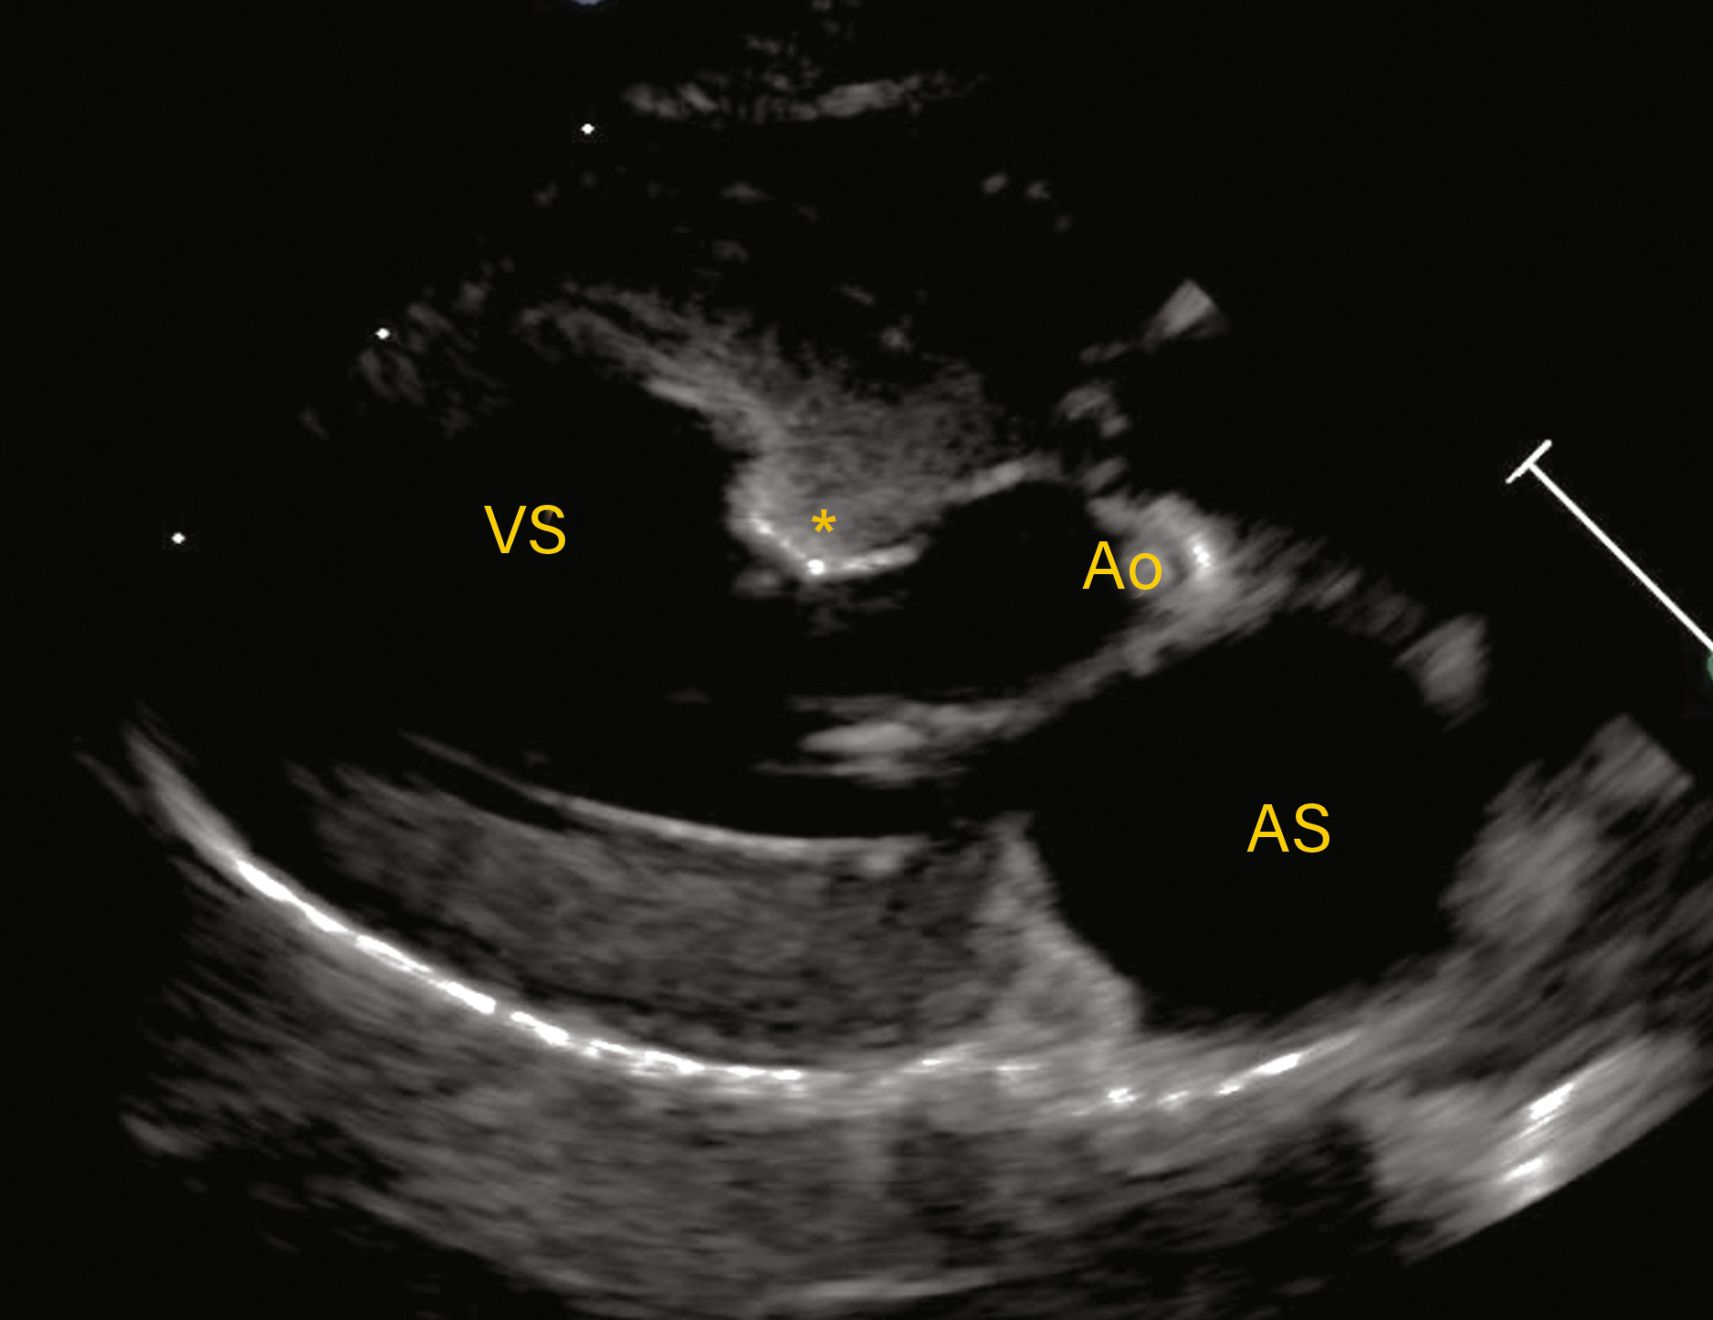

Observațiile ecocardiografice ale HCM pot să prezinte o mare variabilitate.

Figura 2a. Observațiile ecocardiografice ale HCM pot să prezinte o mare variabilitate. Vizualizare parasternală dreaptă în ax lung cu 5 camere prezentând o regiune focală de hipertrofie care afectează septul bazal (*).

Credit: Catheryn Partington Joanna Dukes-McEwan

Vizualizare parasternală dreaptă în ax lung cu 5 camere care arată hipertrofia localizată la nivelul septului bazal (*) ca fiind cauza LVOTO.

Figura 3b. . La pisicile cu CMH suflurile sunt cel mai adesea rezultatul obstrucției tractului de ejecție al ventriculului stâng (LVOTO). Vizualizare parasternală dreaptă în ax lung cu 5 camere care arată hipertrofia localizată la nivelul septului bazal (*) ca fiind cauza LVOTO.

Abrevieri: Ao, aorta; LA, atriul stâng (AS); LV, ventriculul stâng (VS)